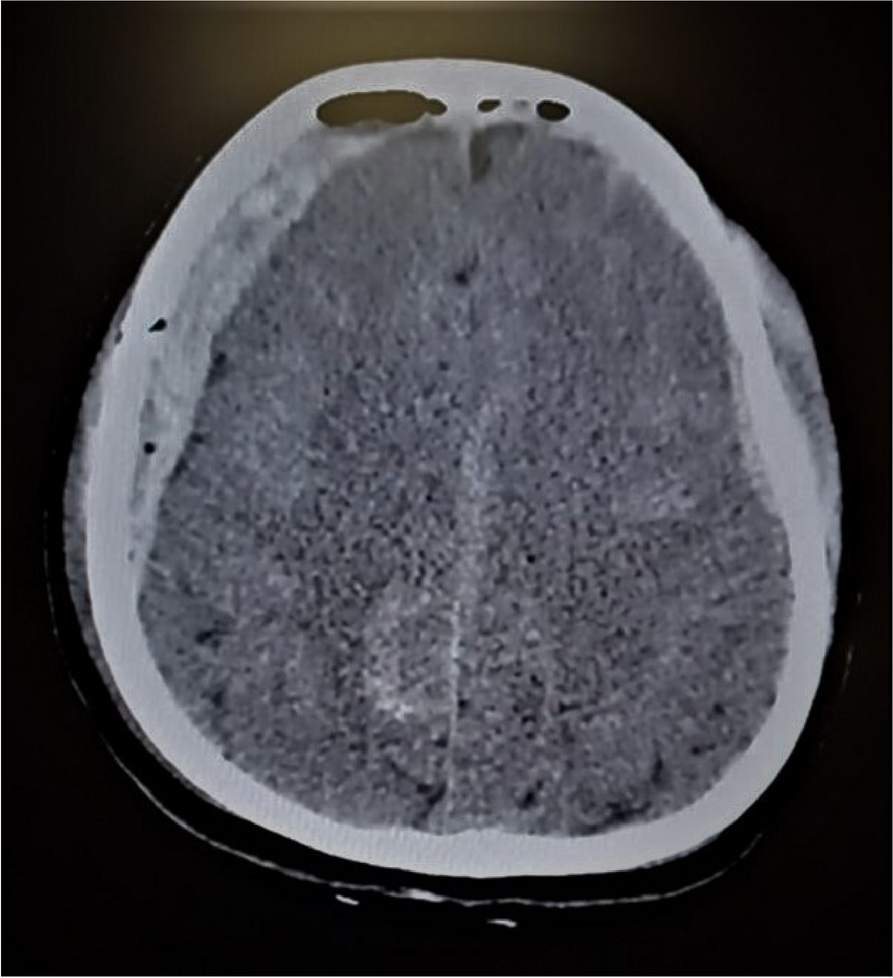

A few hours after the admission in ICU he reported a blunt abdominal pain, mainly on the right side, nausea and the exams showed increased amylase levels, urologists excluded any surgical involvement of pancreatic tissue and suspected a transient sphincter of Oddi dysfunction [3]. After one night in ICU he was transferred to the urology ward due to his clinical stability, even though Amylase peaked at 2340 U/l. Two days later abdominal pain increased to severe, with characteristics of peritonism and increased inflammatory markers. An abdomen-thorax CT scan revealed acute pancreatitis (AP) (Figure 1) and he was transferred to ICU. He started a standard treatment for acute pancreatitis and antibiotic therapy [4].

On postoperative day nine, due to general deterioration of clinical conditions and further anemization that required blood transfusion, he underwent an emergency laparotomy, in which propofol was not used as an anesthetic drug, that found a completely necrotic pancreas. The following day he faced a multi organ failure (MOF) which rapidly led to death. Consent to publish the case report was accorded by the family.

Acute pancreatitis (AP) Is a complex and severe disease with a high mortality rate [4]. Propofol, is a common anesthetic drug which is widely used in daily practice for sedations and general anesthesia [5], few cases of Propofol Induced AP have been published, in which the diagnosis has been made excluding more common causes [6].

In fact, Propofol is listed as a possible cause of AP, class Ib, based on the classification of Badalov et al. [7]. Following the scheme proposed by the systematic review by Haffar et al for Propofol induced AP [6] we could confirm that our hypothesis is plausible. He satisfied the American College of Gastroenterology criteria for AP [8,9] and it is classified as severe acute pancreatitis according to the Revised Atlanta Classification with peripancreatic necrotic fluid collection [10]. Marshall score [11] after admission was two and Naranjo et al [12] probability scale for drug adverse reaction was three, meaning that the adverse reaction is possible. Latence according to Badalov et al [7] has been short or intermediate. Exclusion of other plausible causes, timing of pancreatitis symptoms and previous cases in literature support our hypothesis of propofol induced pancreatitis.

Fig. 1 (abstract A21).

See text for description

Bild vergrößern